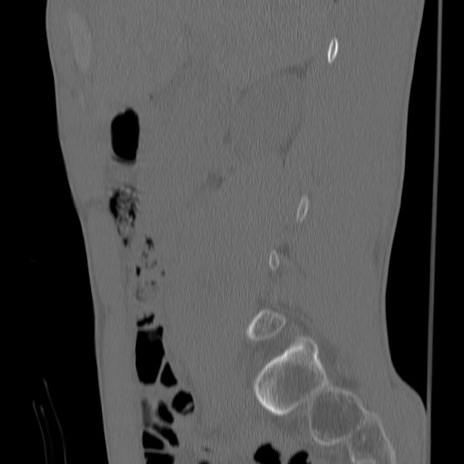

症例3 腰椎CT(矢状断像)

【症例】30歳代男性

【主訴】腰痛

【現病歴】本日旅行先で観光中に、友人と衝突し転倒し受傷。

【身体所見】麻痺なし、右下腿内側前面外側、左下腿内側に知覚鈍麻・しびれ

異常所見と診断は?

腰椎CT